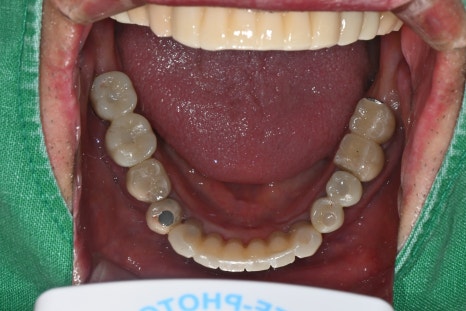

오른쪽 사진: 발치한 자리에 식립한 임플란트에 최종 보철이 정확히 체결된 모습입니다.

오른쪽 사진: 아랫니는 빠진 크라운과 부러진 임플란트가 있어 전반적인 재정비가 필요했습니다.